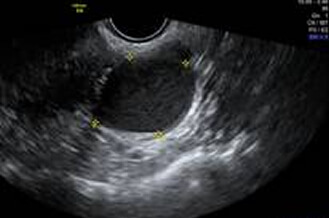

正常卵巢

超音波探頭伸入陰道後,可以縮短探頭與子宮和卵巢的距離,看到子宮和卵巢更多的細節。檢查約2~3分鐘內可完成。